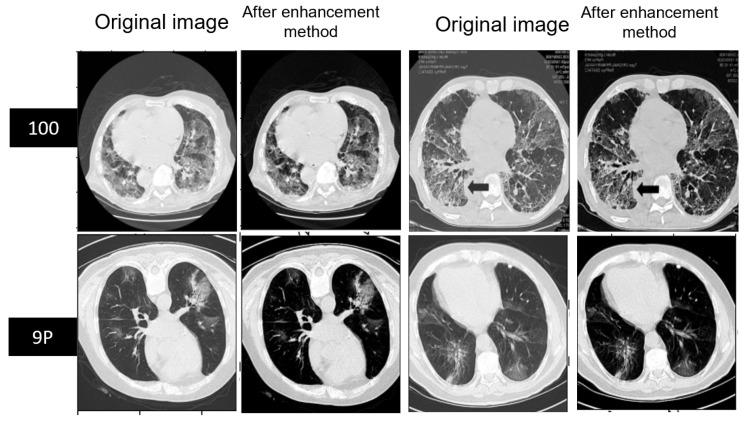

The disaster of the COVID-19 pandemic has claimed numerous lives and wreaked havoc on the entire world due to its transmissible nature. One of the complications of COVID-19 is pneumonia. Different radiography methods, particularly computed tomography (CT), have shown outstanding performance in effectively diagnosing pneumonia. In this paper, we propose a spatial attention and attention gate UNet model (SAA-UNet) inspired by spatial attention UNet (SA-UNet) and attention UNet (Att-UNet) to deal with the problem of infection segmentation in the lungs. The proposed method was applied to the MedSeg, Radiopaedia 9P, combination of MedSeg and Radiopaedia 9P, and Zenodo 20P datasets. The proposed method showed good infection segmentation results (two classes: infection and background) with an average Dice similarity coefficient of 0.85, 0.94, 0.91, and 0.93 and a mean intersection over union (IOU) of 0.78, 0.90, 0.86, and 0.87, respectively, on the four datasets mentioned above. Moreover, it also performed well in multi-class segmentation with average Dice similarity coefficients of 0.693, 0.89, 0.87, and 0.93 and IOU scores of 0.68, 0.87, 0.78, and 0.89 on the four datasets, respectively. Classification accuracies of more than 97% were achieved for all four datasets. The F1-scores for the MedSeg, Radiopaedia P9, combination of MedSeg and Radiopaedia P9, and Zenodo 20P datasets were 0.865, 0.943, 0.917, and 0.926, respectively, for the binary classification. For multi-class classification, accuracies of more than 96% were achieved on all four datasets. The experimental results showed that the framework proposed can effectively and efficiently segment COVID-19 infection on CT images with different contrast and utilize this to aid in diagnosing and treating pneumonia caused by COVID-19.

由于其传染性,新冠疫情这场灾难已夺去无数生命并给全世界造成了严重破坏。新冠病毒肺炎是新冠疫情的并发症之一。不同的影像学方法,尤其是计算机断层扫描(CT),在有效诊断肺炎方面表现出色。在本文中,我们受空间注意力UNet(SA - UNet)和注意力UNet(Att - UNet)启发,提出了一种空间注意力与注意力门控UNet模型(SAA - UNet),以解决肺部感染分割问题。所提出的方法应用于MedSeg、Radiopaedia 9P、MedSeg与Radiopaedia 9P的组合以及Zenodo 20P数据集。在上述四个数据集上,该方法显示出良好的感染分割结果(两类:感染和背景),平均Dice相似系数分别为0.85、0.94、0.91和0.93,平均交并比(IOU)分别为0.78、0.90、0.86和0.87。此外,它在多类分割中也表现良好,在四个数据集上的平均Dice相似系数分别为0.693、0.89、0.87和0.93,IOU分数分别为0.68、0.87、0.78和0.89。所有四个数据集的分类准确率均超过97%。对于二元分类,MedSeg、Radiopaedia P9、MedSeg与Radiopaedia P9的组合以及Zenodo 20P数据集的F1分数分别为0.865、0.943、0.917和0.926。对于多类分类,所有四个数据集的准确率均超过96%。实验结果表明,所提出的框架能够有效且高效地分割不同对比度CT图像上新冠病毒感染情况,并利用这一点辅助诊断和治疗新冠病毒引起的肺炎。